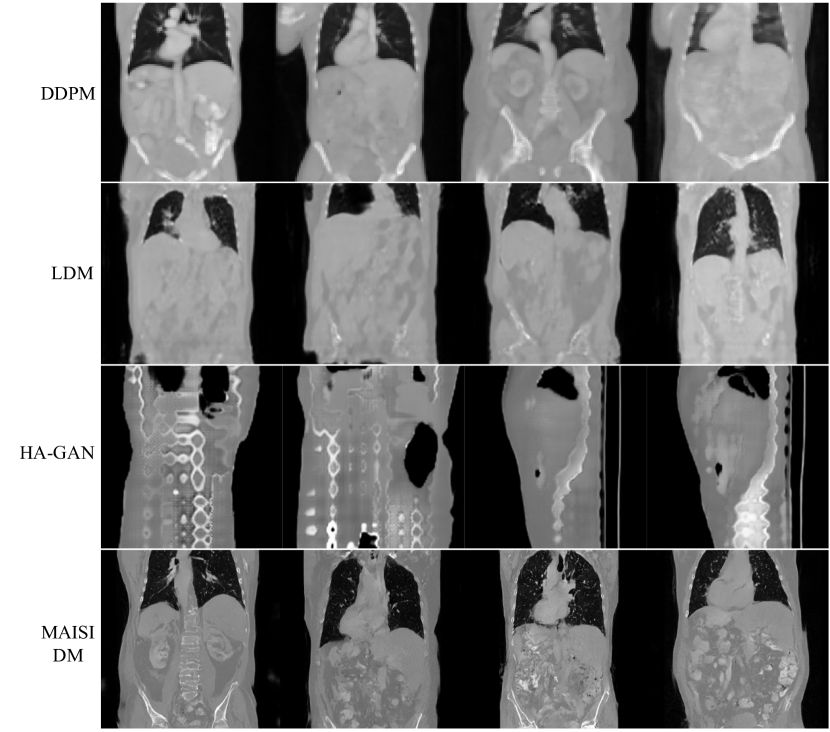

- Synthesis quality : 실제 dataset과 비교하였을 때 FID 수치 비교

- DDPM, LDM, HA-GAN과 비교하였을 때 실제 dataset과 유사한 이미지를 생성.